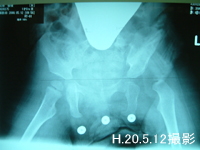

治療は脱臼をしている左足を2.5キロ、脱臼していない右足を2キロのおもりで牽引。そして12日に撮ったレントゲンの結果、下がったのは3ミリ、まだまだ足りないので夜だけ更に重りを500グラム増やし左足3キロ、右足2キロでしばらく頑張ってまたレントゲン撮影することになる。